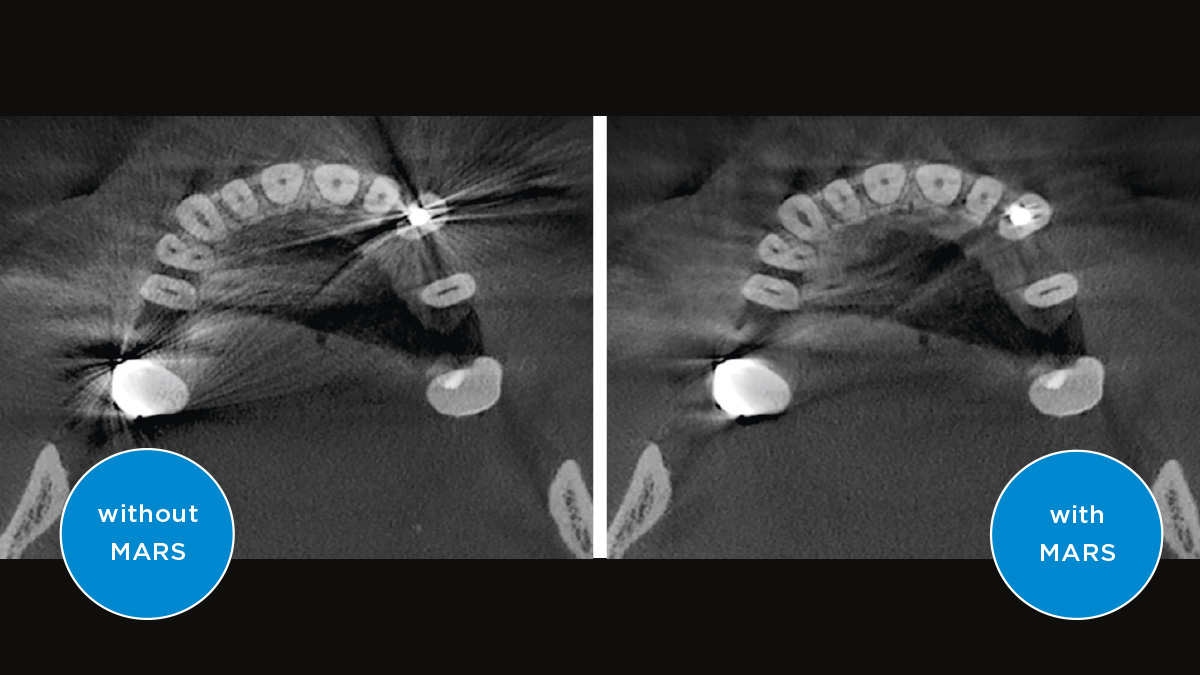

El enfoque correcto es crucial para excelentes radiografías panorámicas. Con la función de autofoco, usted recibirá automáticamente una imagen con la mejor nitidez posible en foco. Los dispositivos de radiología de Dentsply Sirona toman varios miles de imágenes individuales en un ciclo e identifican automáticamente las áreas donde la mandíbula está posicionada de manera óptima. Luego, sin ningún paso manual adicional, estas imágenes se muestran en una nítida imagen final.

Solo algunas partes de la imagen están en foco, mientras que otras áreas están borrosas.

El sistema detecta las áreas relevantes a partir de varios miles de imágenes individuales en un ciclo e identifica automáticamente las áreas donde la mandíbula está posicionada de manera óptima.

Imágenes nítidas.